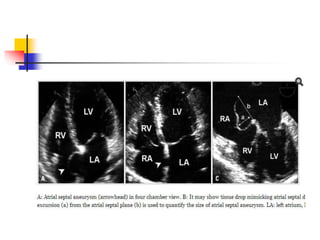

Atrial Septum Variants: Atrial

Septal Aneurysm

 Atrial septal aneurysm (ASA) is found in 1% of adults

at autopsy.

 An excursion of > 10 mm beyond the plane of

interatrial septum is recognized as ASA,although

such cut-off value is arbitrary.

 ASA may involve only the region of fossa ovalis, or

the entire interatrial septum.

 Frequent a/w ASD, PFO, MVP, Marfan syndrome

suggests that ASA is congenital malformation with

genetic background.

 In echo, redundant IAS bulges beyond the atrial

septal plane . Phasic oscillation along the cardiac or

respiratory cycle is common.

 Prominent ASA may appear as cystic mass in long

axis views, but diagnosis is rarely difficult particularly

with the aid of TEE.

 ASA is known to be a/w atrial arrhythmia & ischemic

stroke.

 ASA is frequently accompanied by PFO causing

embolic events, and ASA itself was known as an

independent predictor of cryptogenic stroke.